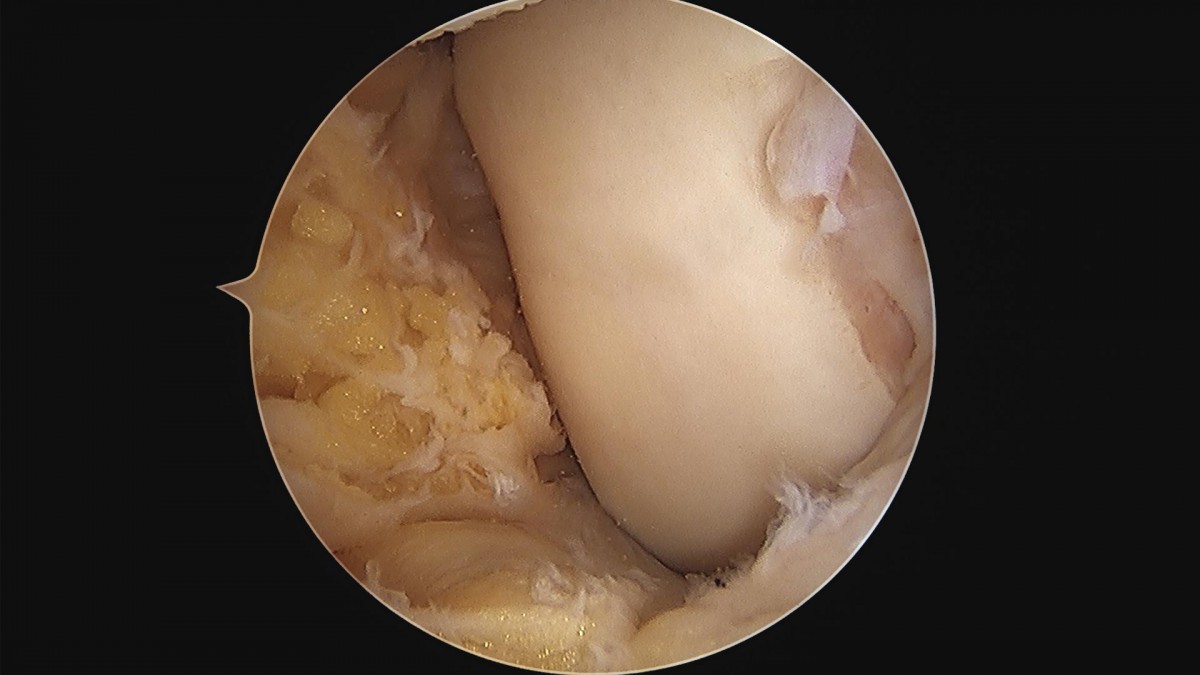

이재상원장님 무릎 내측 반월상 연골판 부분절제술 및 경골 교정술 정순O 환자